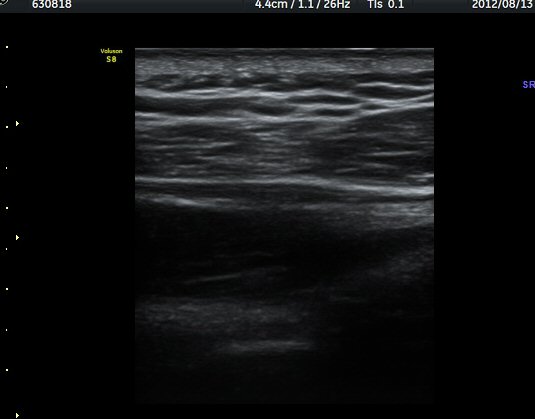

ÈíÀÎ 14ÀÏ ÈÄ ÃÊÀ½ÆÄ°Ë»ç¿¡¼­ ¾à°£ÀÇ ³¶Á¾ Å©±â °¨¼Ò°¡ °üÂûµÈ´Ù(±×¸² 7, 8)